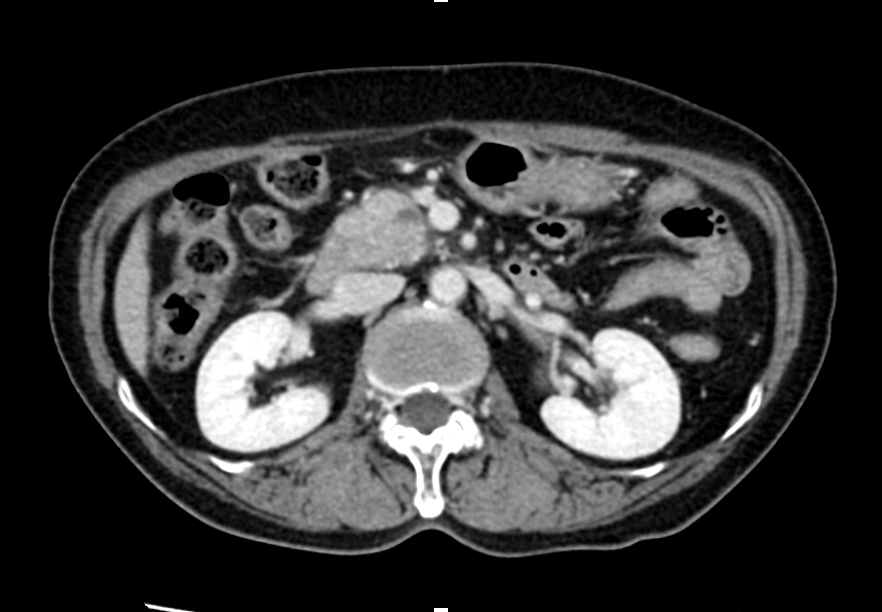

CT

1. Multiphase CT and MRI

- These are standard first-line imaging techniques that provide high-resolution visualization of pancreatic masses, local invasion, and metastatic spread.

- Multiphase CT (pancreatic protocol) remains the backbone for tumor staging and surgical planning.